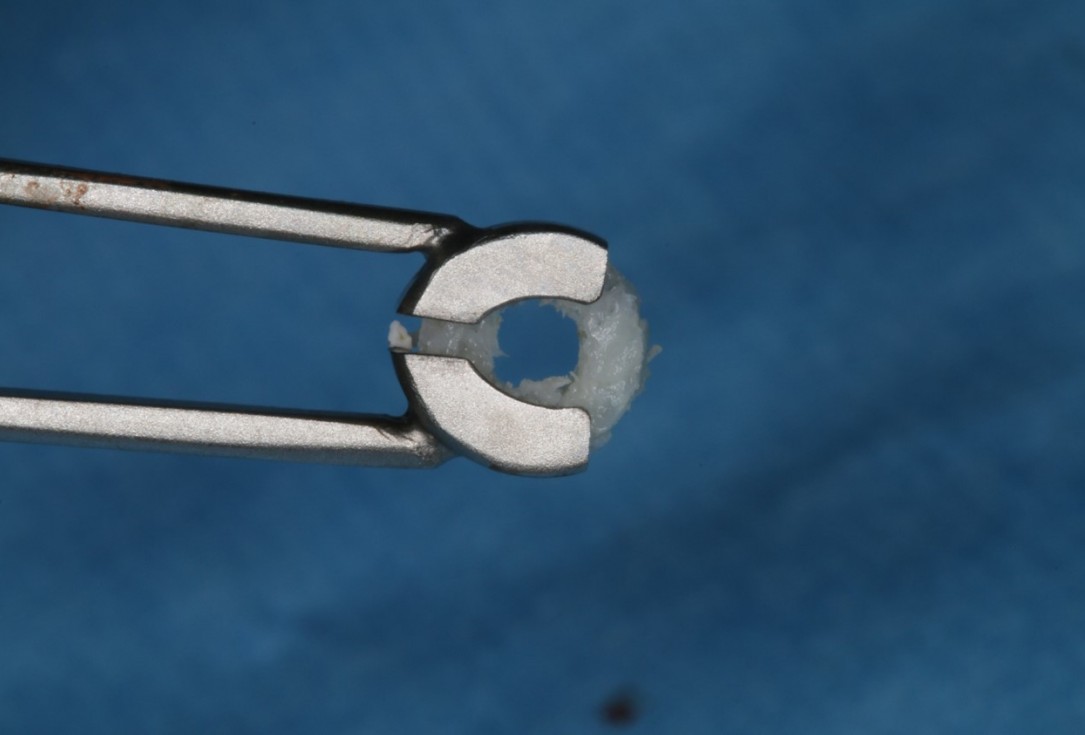

Initial situation: X-ray scan reveals eggshell thin sinus floor (1-3 mm) on both sites of the maxilla; green areas indicate the planned maxgraft® bonerings and red areas the planned implants